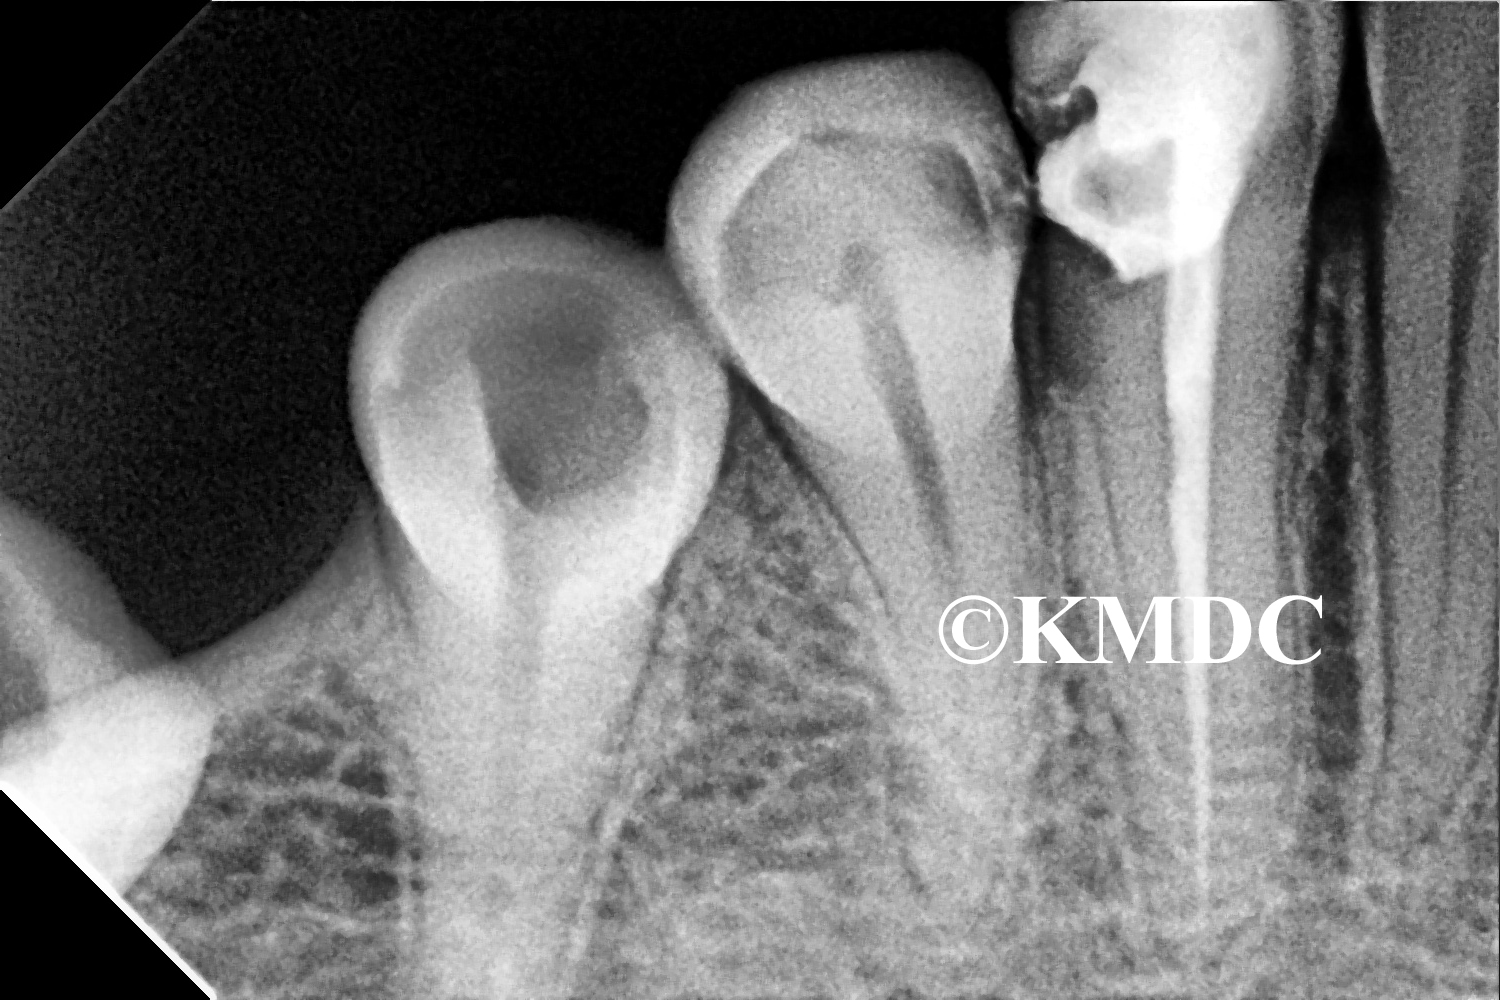

Clinical Gallery